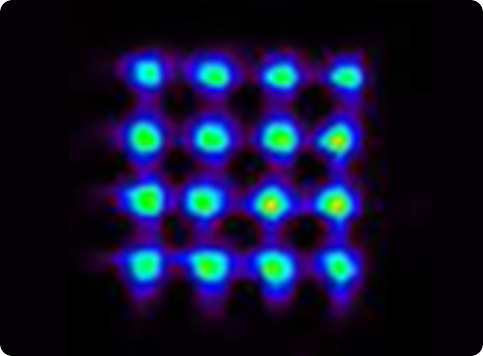

Several crystal-APD units and the corresponding frontend electronics are assembled in detector modules. Our APD-based detector module has 384 LYSO 2x2x20 mm crystals and covers a detection area of ~4x8 cm. One of the advantages the APDs is the capability of performing the double readout of the scintillation crystals, which allows to calculate the DoI of the detected photons. Associated to the fine detector pitch (2x2 mm) and the one-to-one coupling between crystal and APD pixels, the DoI capability permits an excellent spatial resolution of the order of 1.3 mm over the whole Filed-of-View.

Clear-PEM double readout scheme allows calculation of photon Depth of Interaction (DOI) and compensates blurring due to the parallax effect in PET resulting in an isotropic image resolution of 1.3 mm FWHM.